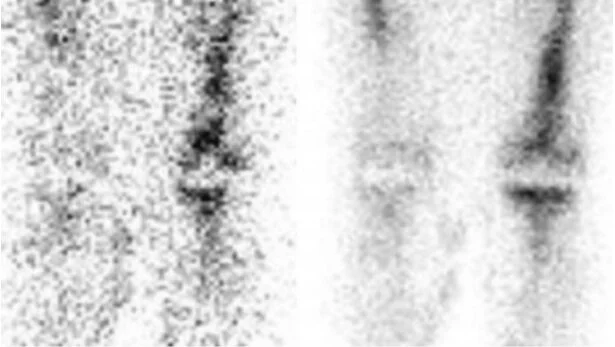

The patient underwent a bilateral total knee replacement. Two years later he represents with left knee pain but normal WBC count and mildly raised inflammatory markers. There is clinical suspicion for prosthetic infection, so In-111 WBC (left) and Tc99-Sulfur Colloid (right) scans are performed together for evaluation.

The In-111 WBC scan is sensitive for inflammation, however false positives can occur in the setting of aseptic loosening. In order to improve specificity when concerned for osteomyelitis, a Tc99-Sulfur Colloid scan be performed simultaneously. On the Sulfur Colloid scan, areas of increased uptake on the WBC scan that represent infection should show decreased uptake. Increased uptake on both studies is therefore suggestive against infection.